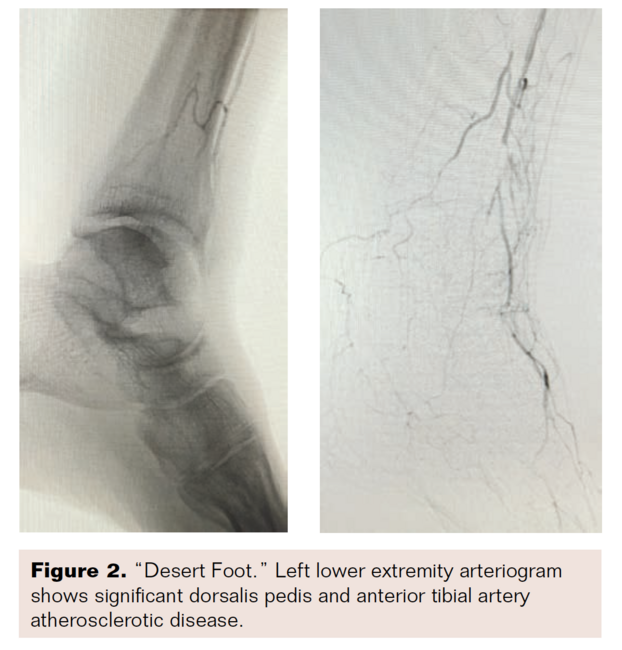

Noninvasive studies in the vascular laboratory demonstrated triphasic popliteal waveforms, monophasic waveforms at the PT and DP with diminished toe pressures, and severely dampened arterial waveforms at the digital level. Ankle-brachial index/toe-brachial index (ABI/TBI) was 1.18/0.7 on the right and 0.99/0 on the left. Combination CO2 and contrast arteriography revealed severe pedal arterial disease that was not amenable to retrograde pedal access or bypass surgery (Figure 2). Arterial anatomy was patent to the popliteal level with PT and peroneal arterial caliber greatly diminished beyond the trifurcation. Both arteries were occluded at the mid-calf level with minimal plantaris pedis collateralization. The distal anterior tibial (AT) artery was occluded at the ankle level with reconstitution of a segment of the DP and the first tarsal branch. In order to perfuse the forefoot, an AT thrombo-endarterectomy with patch angioplasty and an end-to-end AT tibial reconstruction from the DP segment to the AT tarsal branch at the metatarsal level was performed (Figure 3). This resulted in a palpable DP pulse.

Among patients with CLI, the most difficult to treat are those with severe infrapopliteal or below-the-knee (BTK) arterial occlusive disease, and increasingly, patients with pedal disease. Pedal bypass has been well recognized in the past. Vein bypass to the DP or plantar branches of the posterior tibial artery have met with good success.23,24 In a retrospective study of over 1000 cases of DP bypasses, primary patency rates were reported at up to 56.8%.23 In the same study, saphenous vein grafts had the best outcomes with secondary patency rates of 67.6%.23 Similar patency rates (primary patency rates of 67% at 1 year) were reported in a retrospective study of patients undergoing inframalleolar bypass to plantar artery branches.24 However, limb preservation practices increasingly face the clinical challenge of patients with significant infra-malleoli pedal disease, the so-called “desert foot.” These cases present the challenge of extensive pedal artery disease with no obvious target for distal bypass revascularization, and difficulty with standard endovascular techniques. In order to establish perfusion for limb preservation, aggressive bypass and endovascular techniques are required.